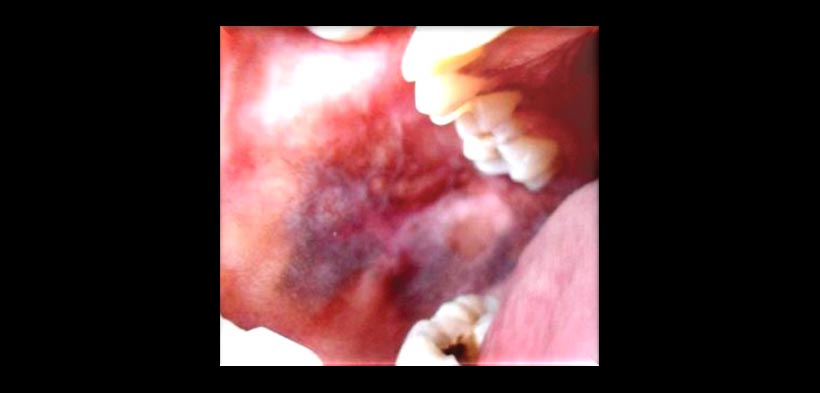

4.- ATROFICO-EROSIVO (fig. 4)

Fig. 5. Liquen plano oral: patrón buloso o ampollar, lesión localizada en la gíngiva palatina de los dientes superiores, se caracterizan por ser lesiones ampollares que posteriormente se ulceran.